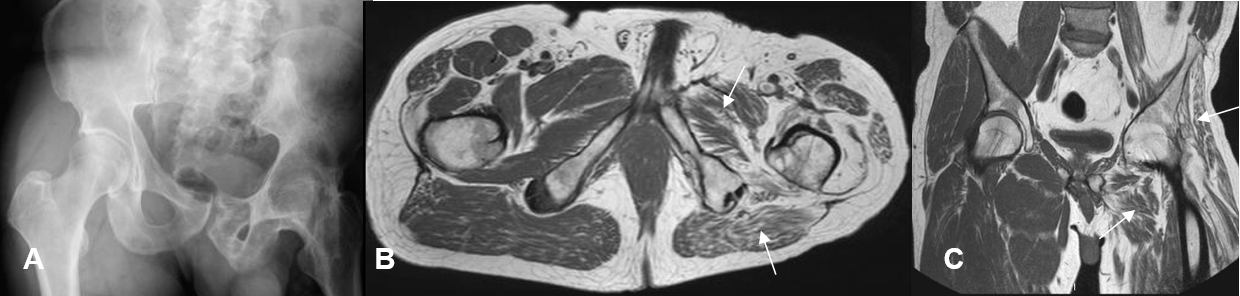

Fig 29 F. Atrofia.

Rx AP. Luxación abandonada de la cadera izquierda. Igual paciente anterior, con atrofia muscular y reemplazo graso, por atrofia muscular.